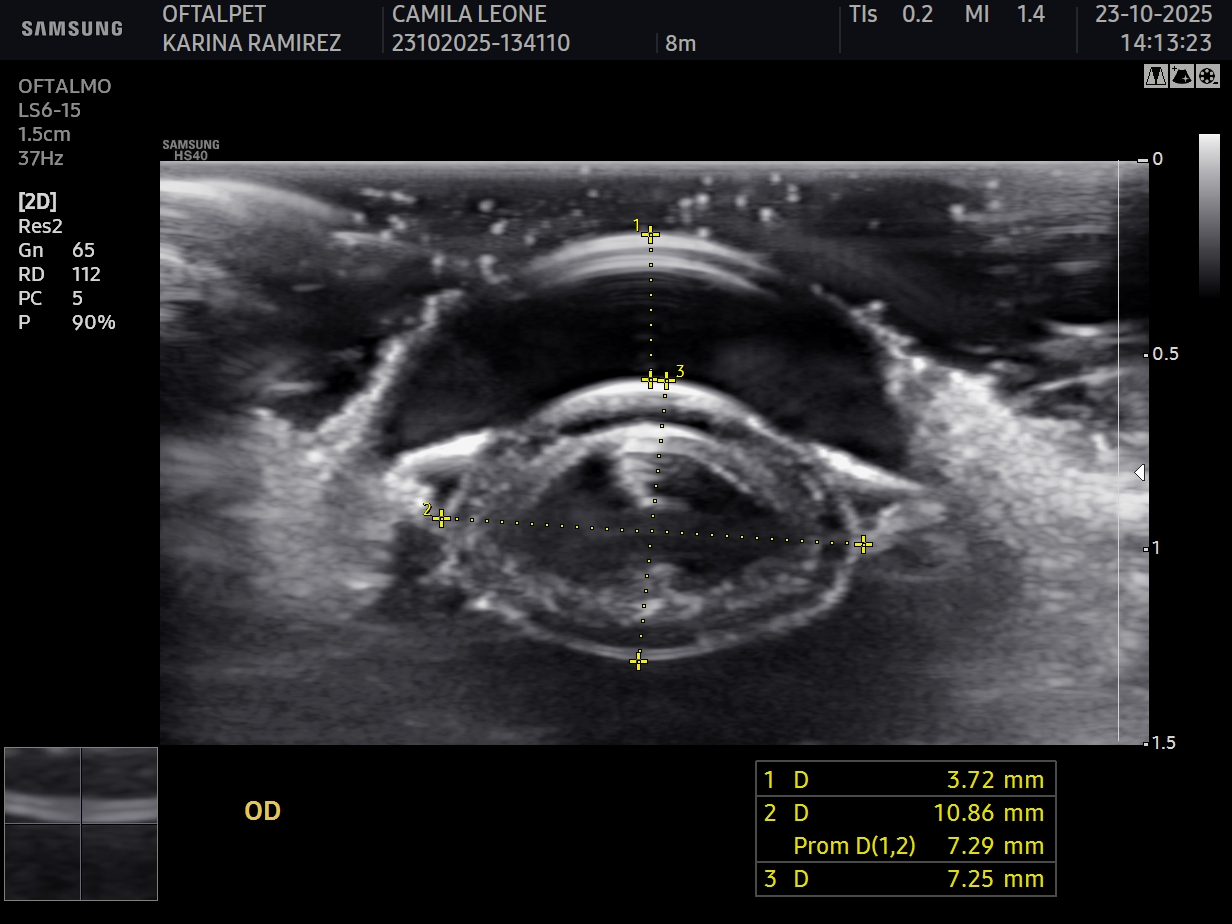

Ecografia